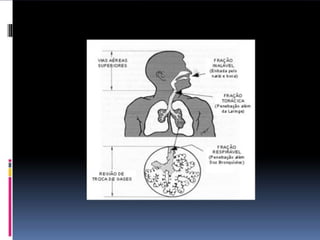

Toda partícula sólida de qualquer tamanho ou origem, formada por trituração ou outra ruptura mecânica de um material original sólido, capaz de manter-se suspensa no ar

0,1-25 micrômetros de diâmetro (>7 micrômetros)

Partículas líquidas (gotículas - >0,5 micras/2-6 micrômetros) produzidas mecanicamente (processo spray/dispersão)

Partículas líquidas (gotículas – 0,01-10 m/<0,5 micras) geradas pela condensação de um estado gasoso (vapores), passagem rápida de ar nos líquidos ou desintegração de um estado líquido (ebulição)  > difusão que os fumos

Partículas sólidas (0,01-0,5 micrômetros / 0,5 micras / normalmente <1 micrômetro) resultante do uso industrial de metais, da condensação de vapores ou volatização de metais fundidos; acompanhado de reação química